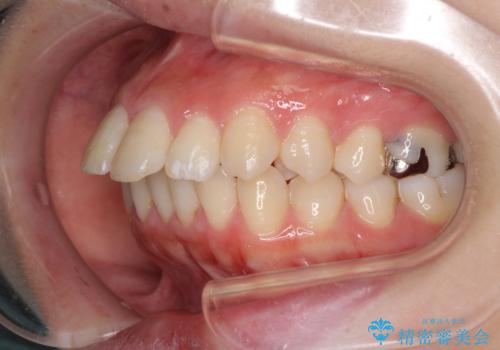

突出した口元が気になる ハーフリンガル装置による抜歯矯正

- ハーフリンガル

- 口元の突出感を気にして来院された患者様です。

通常では上下左右の第一小臼歯4本を抜歯しますが、下顎が左側にシフトしていたため、下顎左側のみ第二小臼歯を抜歯し、正中を合わせながら口元を下げる治療計画としました。

ハーフリンガルは、通常では表側のワイヤー矯正よりも治療期間がかかります。特に今回のように下顎左側をイレギュラーの第二小臼歯抜歯としたため、さらに時間がかかることが予想されました。

実際に治療をおこなってみると、2年を切る短期間で治療を終えることができました。